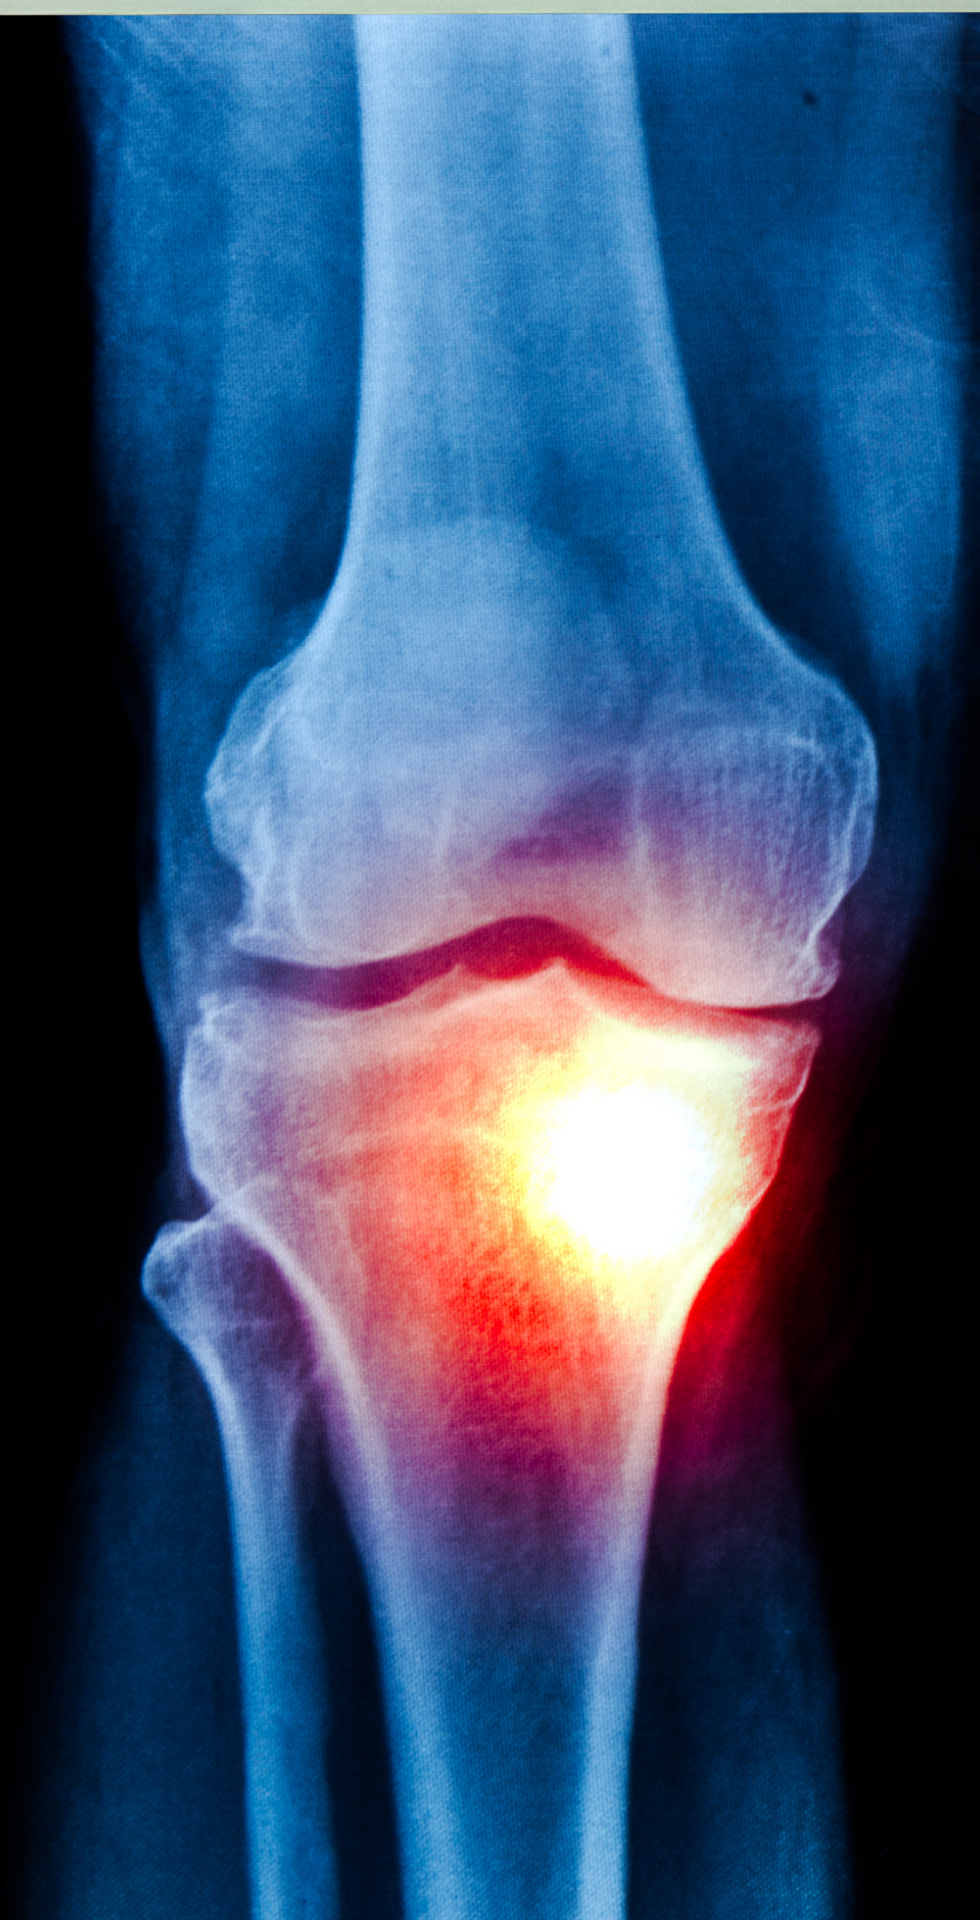

Muchas personas lo atribuyen al cansancio o a la edad, pero en realidad podría tratarse de osteoartritis, un desgaste progresivo en las articulaciones que afecta la movilidad.

Ocurre cuando el cartílago que protege las articulaciones se desgasta, generando fricción entre los huesos.

Es más frecuente a partir de los 50 años, aunque puede aparecer antes si existen factores que la favorecen.